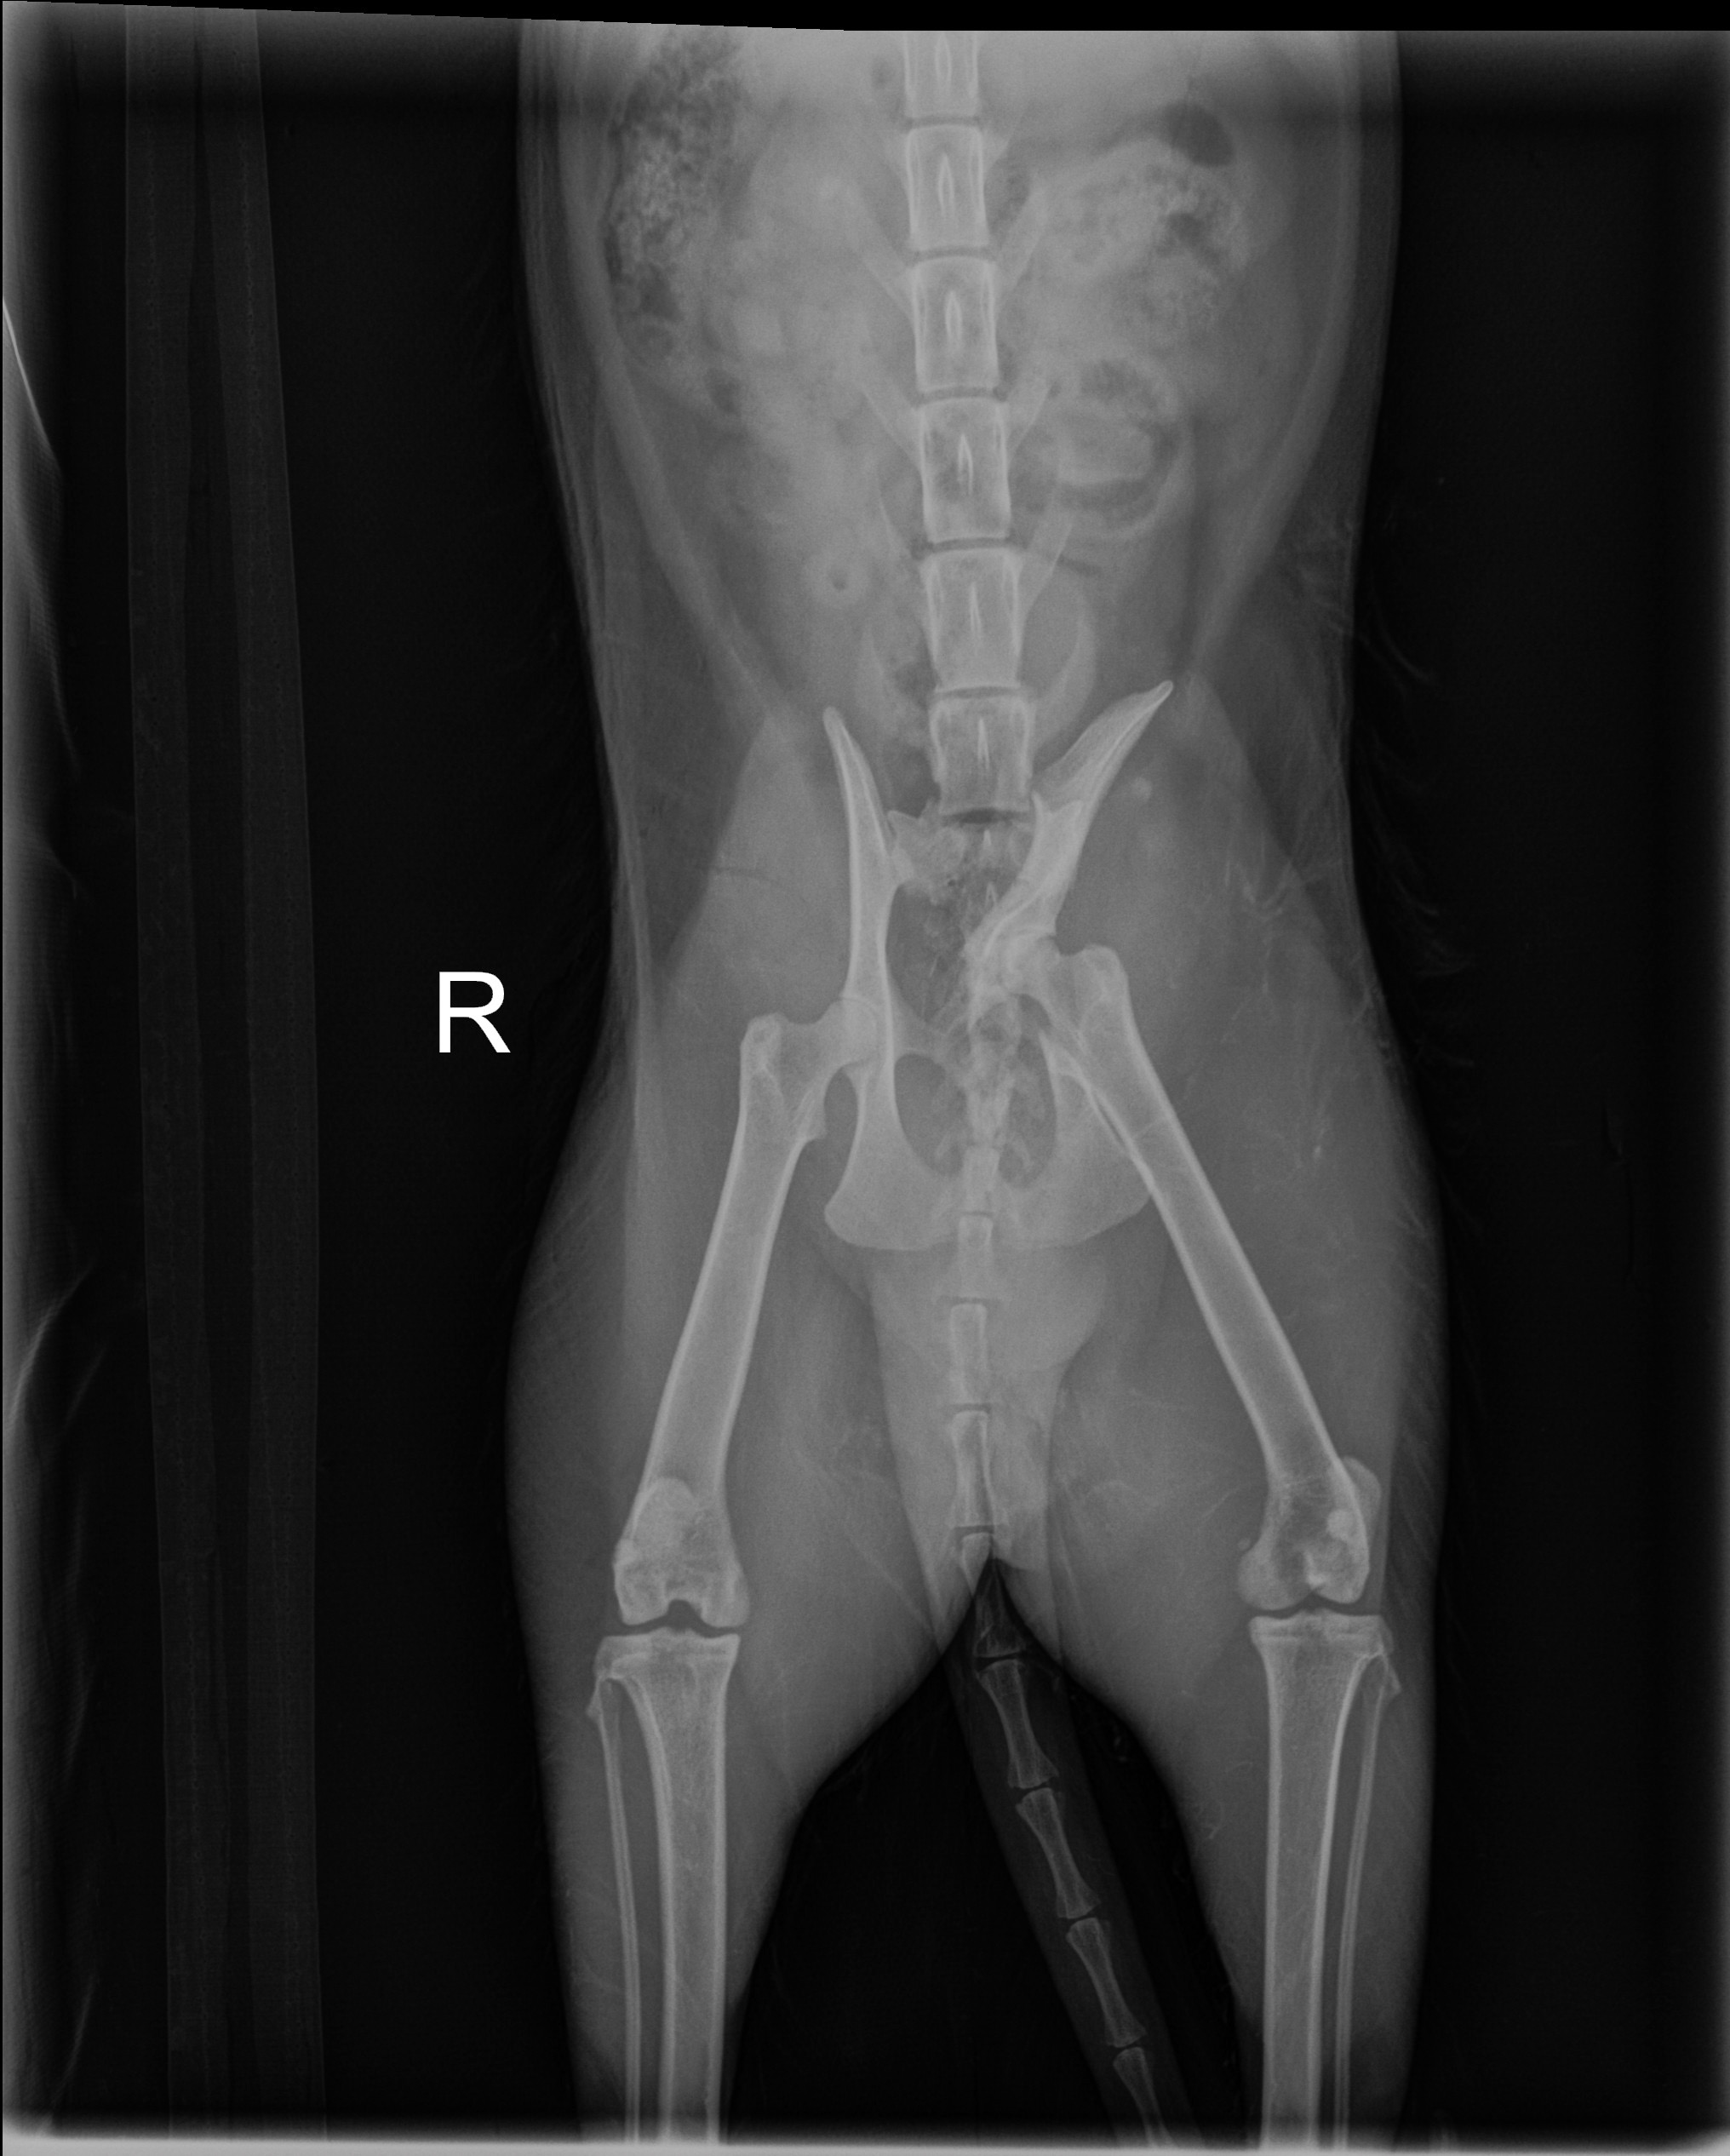

On Sunday morning, when she didn’t show up for breakfast, we knew something was wrong. We soon discovered she had been hit by a driver and left in pain, unable to move. Thankfully, we found her in time to get her the urgent care she needed. Ryobi suffered multiple pelvic fractures and now faces surgery to walk again and return to a normal life.